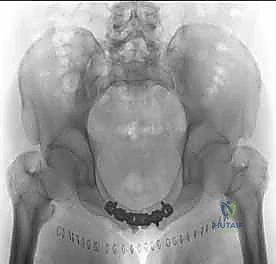

يتم تقييم المريض بشكل شامل (أشعة سينية، أشعة مقطعية ثلاثية الأبعاد) لتحديد حجم الإصابة بدقة. تُجرى العملية تحت التخدير العام لضمان استرخاء العضلات بالكامل وعدم شعور المريض بأي ألم. يتم وضع المريض على ظهره على طاولة العمليات، وتُعقم منطقة البطن والحوض بالكامل.

بمجرد استعادة الوضع الصحيح للعظام، يقوم الدكتور هطيف بتثبيتها باستخدام صفيحة معدنية متخصصة (غالباً صفيحة إعادة بناء متعددة الثقوب مصنوعة من التيتانيوم أو الفولاذ المقاوم للصدأ الطبي). يتم تثبيت هذه الصفيحة عبر المفصل العاني باستخدام مسامير قشرية (Cortical Screws) تُغرس بعمق في عظام العانة الصلبة لضمان تثبيت قوي يتحمل ضغط الجسم.

بعد التأكد من قوة التثبيت من خلال الأشعة السينية داخل غرفة العمليات (Fluoroscopy)، يتم إغلاق الجرح على طبقات باستخدام خيوط جراحية تجميلية قابلة للامتصاص، مع وضع أنبوب تصريف (درنقة) لمنع تجمع السوائل.